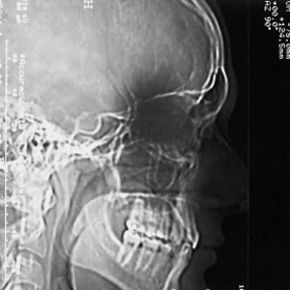

A conventional X-ray image is basically a shadow: You shine a "light" on one side of the body, and a piece of film on the other side registers the silhouette of the bones.

The same thing happens in a conventional X-ray image. If a larger bone is directly between the X-ray machine and a smaller bone, the larger bone may cover the smaller bone on the film. In order to see the smaller bone, you would have to turn your body or move the X-ray machine.

In order to know that you are holding a pineapple and a banana, your friend would have to see your shadow in both positions and form a complete mental image. This is the basic idea of computer aided tomography. In a CAT scan machine, the X-ray beam moves all around the patient, scanning from hundreds of different angles. The computer takes all this information and puts together a 3-D image of the body.